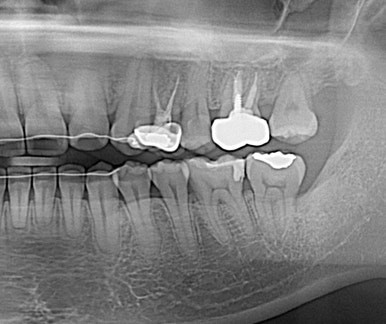

드디어 구강내로 얼굴을 내밀고 제 위치에 안착~

치료 중 임신으로 방사선 사진을 남기지 못해 아쉽지만 기능을 잘해주고 있어 뿌듯하다^^

공교롭게도 이 환자도 27세 여성환자...

일도 힘들었을텐데 꼬박 꼬박 진료도 잘 와줘서 사랑니가 원래 제 자리였던것처럼 위치하고 있다.